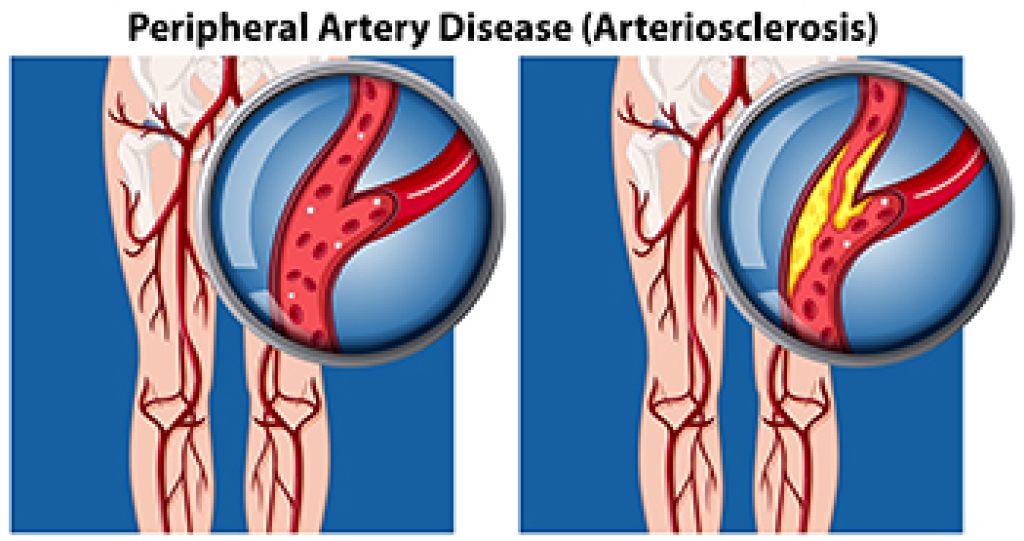

Causes and Risk Factors for PAD

Peripheral artery disease, or PAD, occurs when plaque builds up in the arteries, causing reduced blood flow to the lower limbs. This leads to such symptoms as pain, cramping, or numbness in the feet, toes, or ankles. Smoking, diabetes, high blood pressure, and high cholesterol are major risk factors, while aging and a family history of vascular disease can also contribute to its development. Poor circulation from PAD may cause slow-healing wounds, skin discoloration, and, in severe cases, ulcers that increase the risk of infection or limb loss. A podiatrist can evaluate the blood flow to the feet and ankles, identify complications, and recommend appropriate treatment to help prevent more serious outcomes. Depending on the severity of the peripheral artery disease, treatment may include medical management or procedures like angioplasty or bypass surgery. If you are experiencing foot problems related to peripheral artery disease, it is suggested that you visit a podiatrist for guidance and treatment options.

Peripheral artery disease can pose a serious risk to your health. It can increase the risk of stroke and heart attack. If you have symptoms of peripheral artery disease, consult with one of our podiatrists from Dr. Jeffrey J. Betman & Associates . Our doctors will assess your condition and provide you with quality foot and ankle treatment.

Peripheral artery disease (PAD) is when arteries are constricted due to plaque (fatty deposits) build-up. This results in less blood flow to the legs and other extremities. The main cause of PAD is atherosclerosis, in which plaque builds up in the arteries.

Symptoms

Symptoms of PAD include:

- Claudication (leg pain from walking)

- Numbness in legs

- Decrease in growth of leg hair and toenails

- Paleness of the skin

- Erectile dysfunction

- Sores and wounds on legs and feet that won’t heal

- Coldness in one leg

It is important to note that a majority of individuals never show any symptoms of PAD.

Diagnosis

While PAD occurs in the legs and arteries, Podiatrists can diagnose PAD. Podiatrists utilize a test called an ankle-brachial index (ABI). An ABI test compares blood pressure in your arm to you ankle to see if any abnormality occurs. Ultrasound and imaging devices may also be used.

Treatment

Fortunately, lifestyle changes such as maintaining a healthy diet, exercising, managing cholesterol and blood sugar levels, and quitting smoking, can all treat PAD. Medications that prevent clots from occurring can be prescribed. Finally, in some cases, surgery may be recommended.